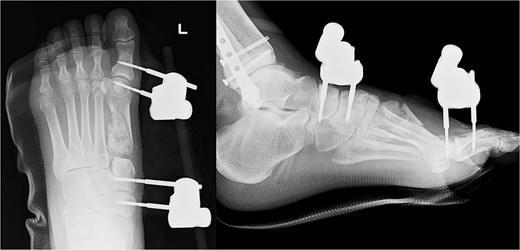

We performed surgery in two stages, owing to the poor condition of the skin. In the first stage, we performed screw fixation for the tibial pilon fracture and plate fixation for the distal fibular fracture. For the first-metatarsal fracture, half pins for external fixation were inserted into the first proximal phalanx, first metatarsal, medial cuneiform, and navicular bone. The external fixator (The Small External Fixation System, Synthes, Oberdorf, Switzerland) was stabilized with the first reduction in the metatarsal shortening deformity (Fig. 2). One week later, the second-stage surgery was performed after the swelling of soft tissues on the dorsum of the foot had improved. A longitudinal skin incision was made on the dorsum of the first metatarsal, and a fusion plate (Variable Angle LCP Forefoot/Midfoot system, Synthes) was placed on the dorsal aspect of the first metatarsal and the medial cuneiform. Three screws were inserted into the medial cuneiform, and four screws were inserted into the distal end of the first metatarsal. Postoperative radiography and CT images are shown in Fig. 3.

Radiography (a, b) and computed tomography (c) images immediately after the second surgery.